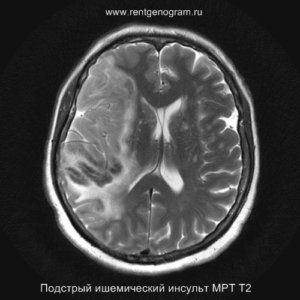

Острая фаза (6 — 24 часа)

В течение острого этапа на МРТ и КТ выявляются все морфологические признаки ишемического инсульта. Область острого ишемического инфаркта визуализируется как зона ↑Т2, ↑Flair, ↑DWI и ↓Т1 ↓ADC. Можно обнаружить тромб в артерии. На КТ в остром этапе также чётко дифференцируется поражённая область, представляющая собой участок с потерей дифференциации мозговых структур и снижением их плотности. Контрастирование в остром периоде не показывает патологических участков с накоплением контраста.

Подострая фаза (24 часа — 6 недель)

На подостром этапе происходит разрушение гематоэнцефалического барьера, что приводит к вазогенному отеку, увеличивая объем ишемического инфаркта, возникновение масс-эффекта и возможного вклинения в случае обширного поражения (например, вклинение поясной извилины под фалькс или миндалин мозжечка в большое затылочное отверстие).